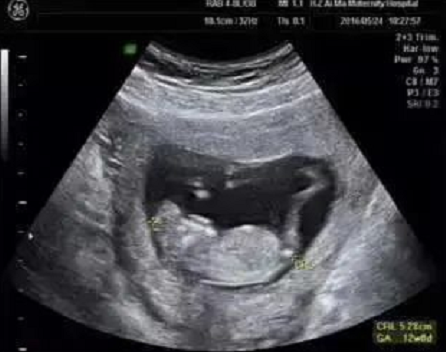

艾玛妇产超声专家团队,在为孕妈妈们做NT检查的同时,对于胎儿的结构也进行了详细的检查,并且发现了多例胎儿严重结构缺陷。

检查选在孕11~13周+6天进行,相当于头臀长45-84mm时测量,超过84mm检查结果会不准确。

NT增厚的胎儿

NT增厚越明显,胎儿异常机会就越高,异常程度也会越严重。般正常的NT厚度不能大于3mm,超过3mm表示NT增厚,存在异常可能。

NT异常增厚的主要原因,可能与胎儿染色体异常有关,比较常见的有2 1-三体、18-三体、13-三体综合征等;也可能是胎儿结构畸形,比如说心脏、骨骼系统发育的异常,但是相对于染色体异常来说,结构畸形或其他原因导致NT增厚占比较小。

另外,还有很多宝宝NT增厚是找不到原因的,如果宝宝染色体是正常的、结构是正常的,那么增厚的NT值会随着孕周的增长慢慢消失、恢复正常,须重视产检复查。